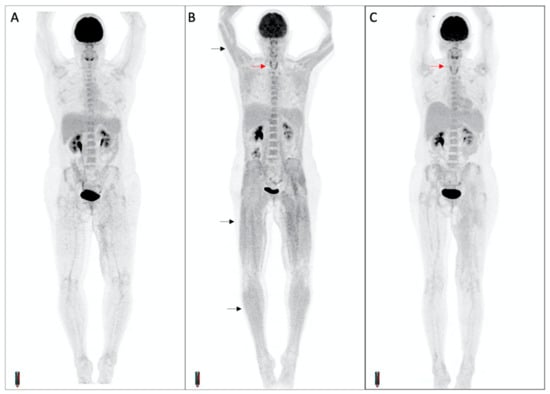

3.5. Concomitant Muscle Uptake